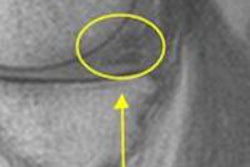

Because conventional MRI sequences do not offer enough specificity, DCE-MRI and DWI are needed differentiate nodular scars from recurrent tumors, according to Fayad.